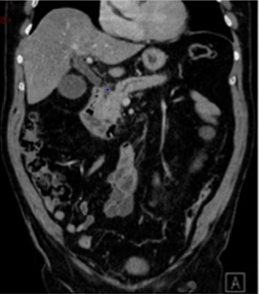

Lésions solides du pancréas